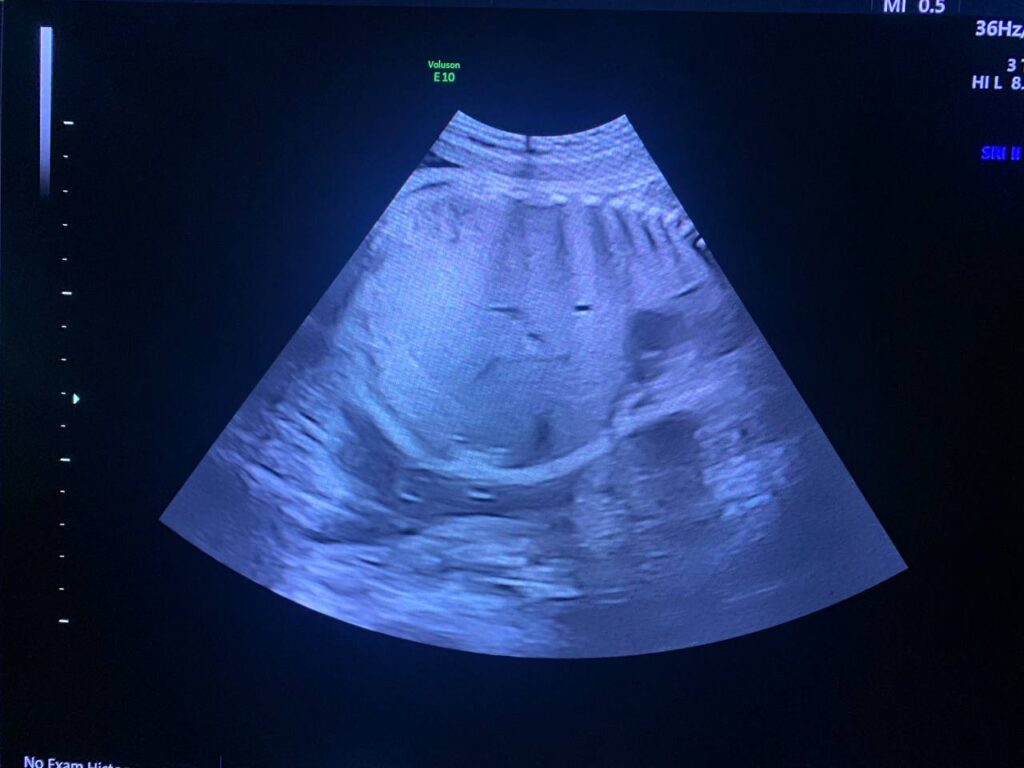

At 29wk pregnancy

Focal aneurysm dilatation of the hepatic umbilical vein 16 in length , 12mm in diamter.

And with Increase in amount of liquor. Amniotic fluid index = 30cm AC =80% , Hepatomegally ?